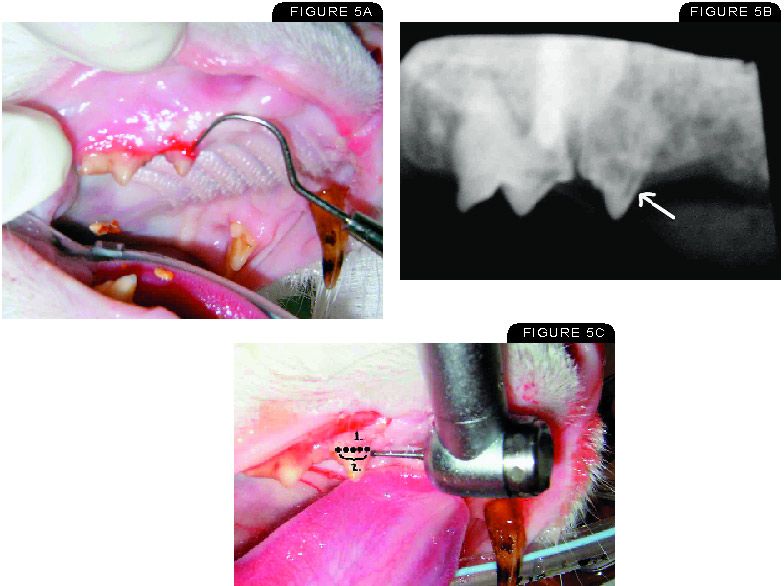

Radiographs of a normal tooth show the root as having a characteristic density and there is a thin dark outline around the root separating it from the bone. Tooth resorption in cats is divided into specific types based on the radiographic X-ray appearance of the root. The first step towards benefiting from the Netstrata difference is to make an enquiry for an obligation free quote.

If you would like to. UNK the. Tooth resorption formerly known as cervical neck lesions or feline oral resorptive lesions is a progressive destruction of the tooth crown andor root resulting in slowly progressive holes in the affected teeth.